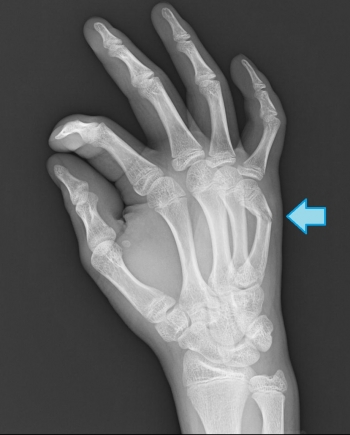

末節骨骨折

指骨の中でも外傷を受ける機会がもっとも多く、手全体の骨折の半分以上を占める。

もっとも頻度の高い指は、中指、次に母指

直達外力によるものが多いが、突き指などの介達外力で発生することも。

深指屈筋腱の付着部により骨片転位が変わる。

マレットフィンガー(ハンマー指変形)

マレットフィンガーは、野球、バレーボールなどの球技の中で、突き指をして発生する。

ベースボールフィンガー、ドロップフィンガーとも呼ばれる

マレットフィンガーの分類

Ⅰ型 終止腱の断裂

Ⅱ型 終止腱の停止部での剥離骨折

Ⅲ型 末節骨の背側関節面の骨折